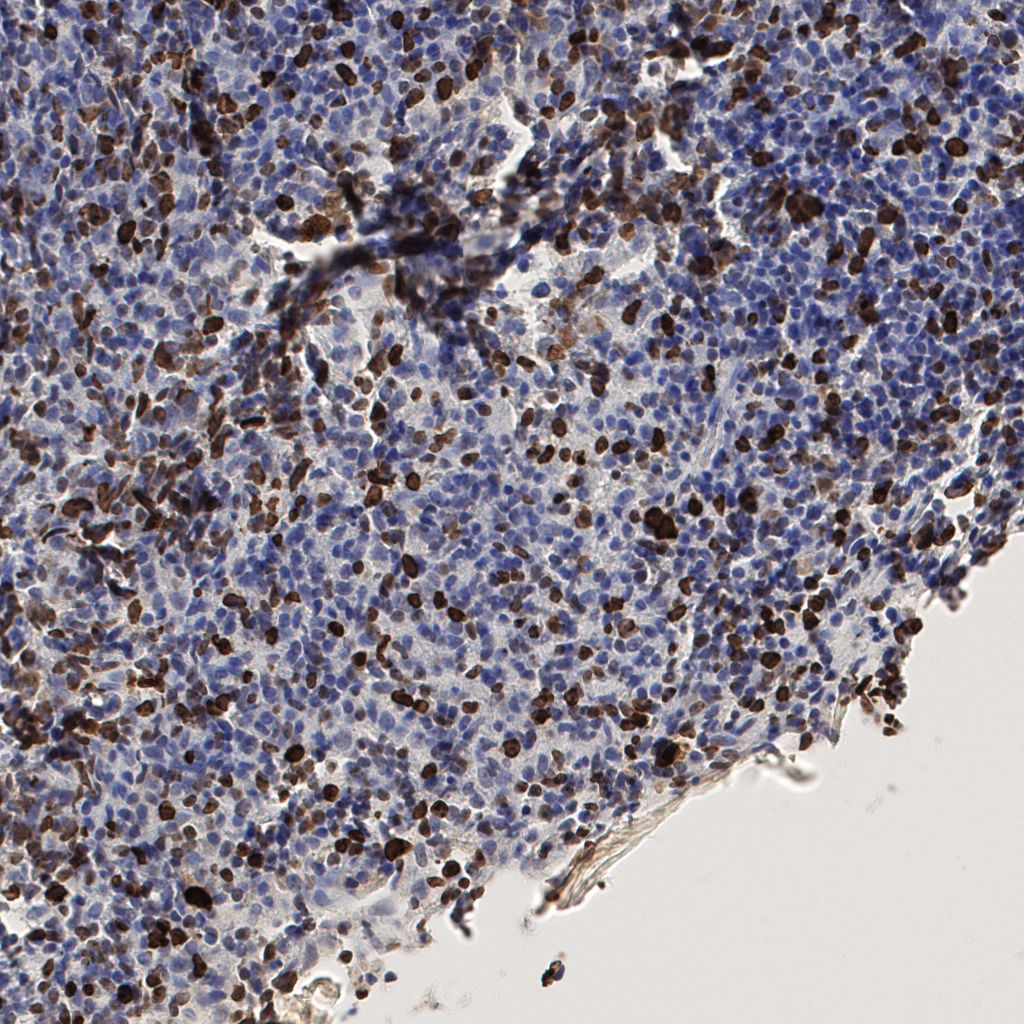

7.85%

Ki67 指数

阴 1104 阳 94